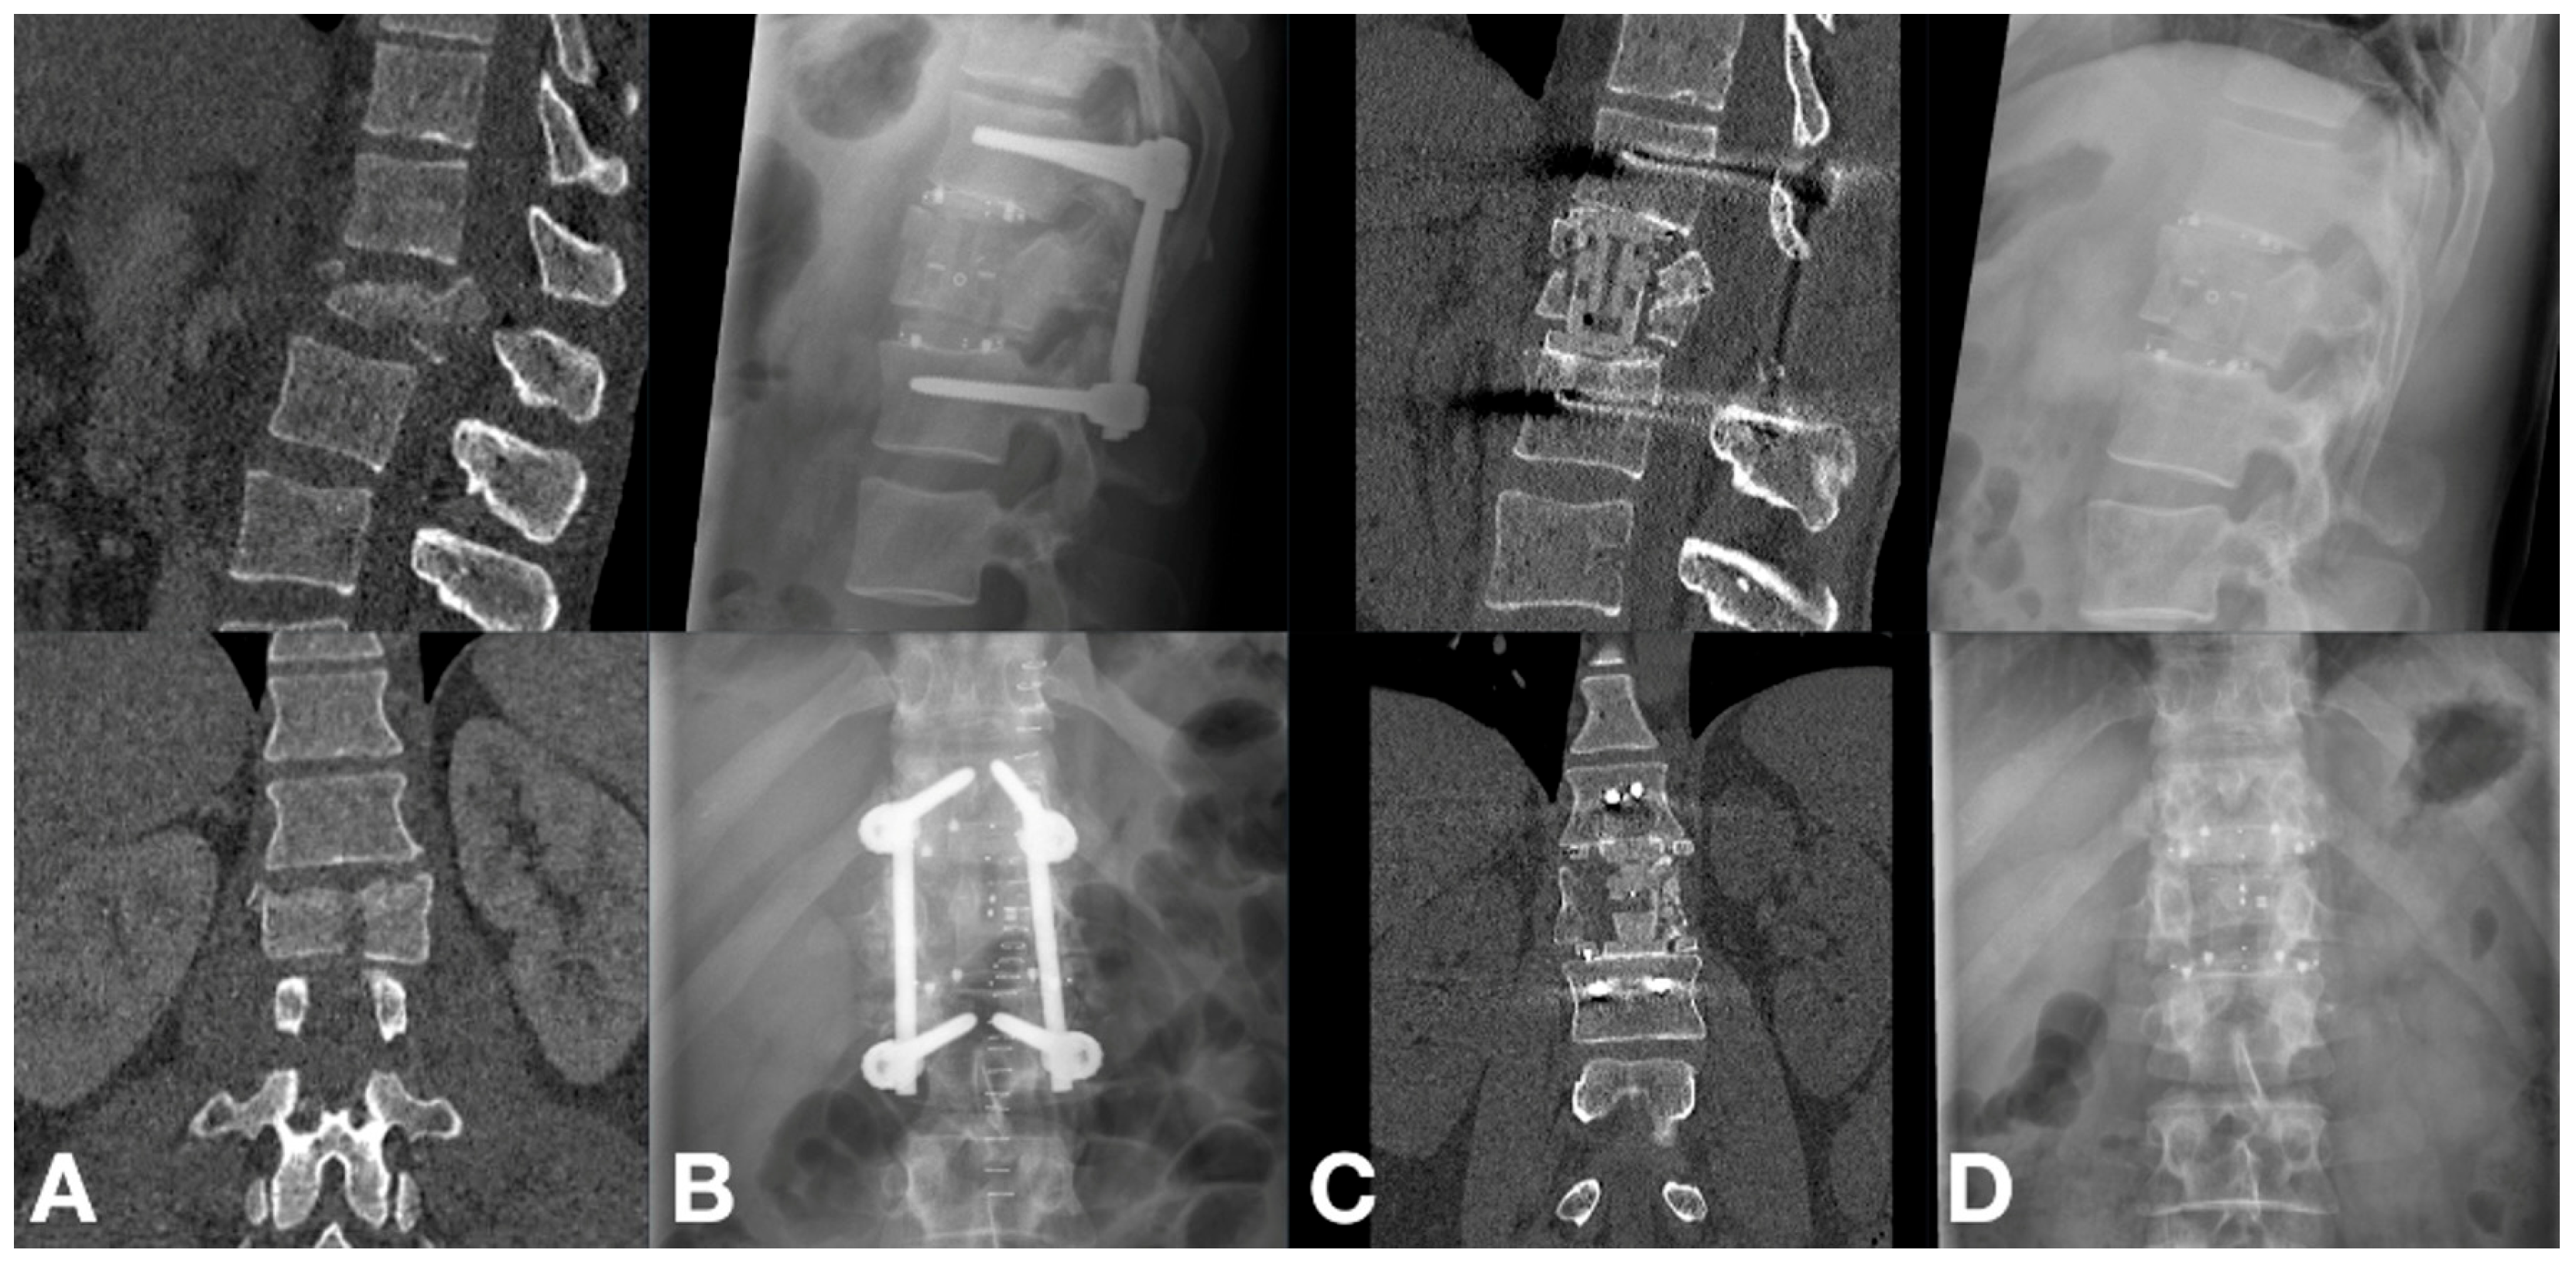

3.2. Radiographic Outcomes

3.3. Clinical Outcomes

4.3. Osseointegration and Fusion Rates